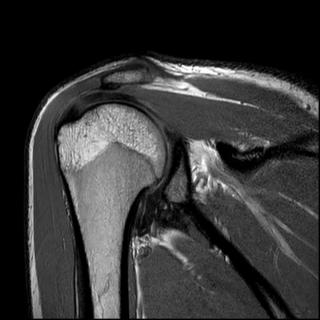

Что показывает МРТ плечевого сустава

Как правило, МРТ плечевого сустава назначается врачом-ортопедом пациентам для исследования таких состояний, как переломы, дегенеративные изменения, суставные повреждения травматического характера, разрывы вращательной манжеты, травмы рабочего характера (например, связанные с вибрацией), травмы спортивного характера, инфекционные и воспалительные процессы, новообразования в мягких тканях и в костях, отеки, болевой синдром, кровотечения вокруг сустава и в мягких тканях, уменьшения возможности движения плеча.